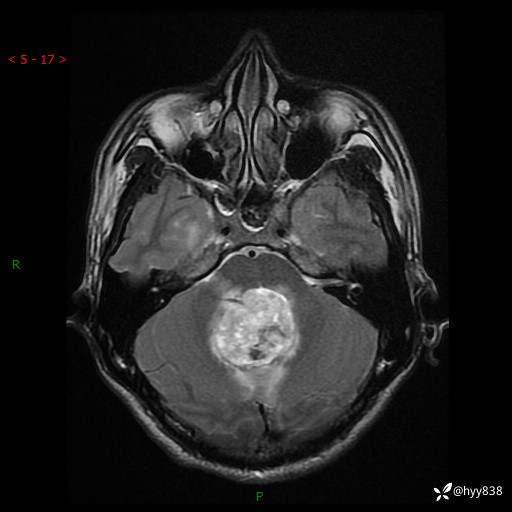

性别:男

年龄:17岁

简要病史:头痛伴间断性呕吐1月余,外院CT提示颅脑占位

颅脑MRI平扫+增强